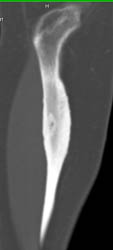

Osteoid Osteoma